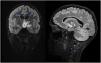

At 2 months of treatment, the neurologic symptoms had resolved and there was significant radiological improvement, with full resolution of the lesion at 5 months (Fig. 3), which confirmed the inflammatory etiology.

Thus, we can conclude that not every intracranial midline lesion is a tumor. Tools such as MRS are useful for the differential diagnosis of these lesions.2,3